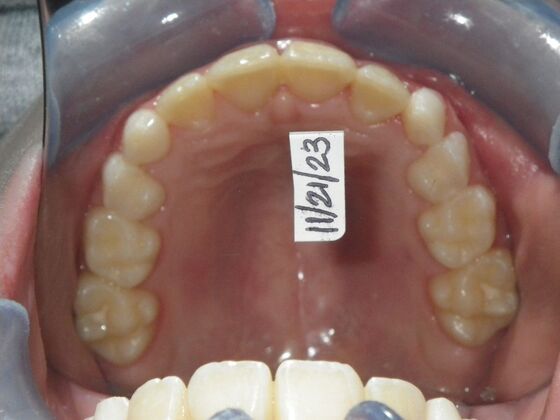

This sweet patient presented with constricted upper and lower arches and blocked out, rotated upper and lower anterior teeth. The upper centrals were leaning backward and had the lower arch captured preventing anterior advancement. Treatment was begun on the upper arch first, followed with placement of lower lip bumper to allow for lateral and anterior development of lower arch. Eventually placed lower brackets with strategic slenderizing of primary teeth to allow permanent incisor to assume their proper placement. All accomplished within 12 months and straight-wire appliances.